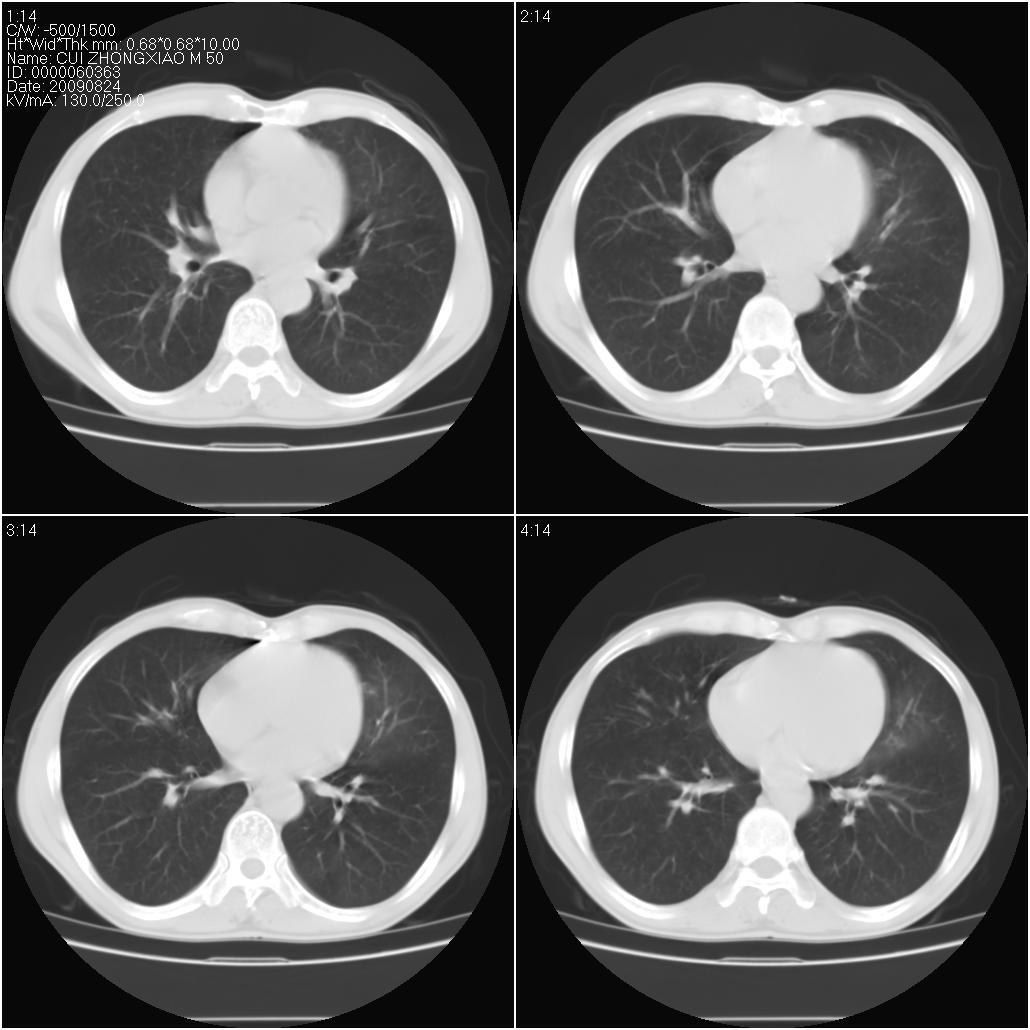

标题: CT21851:男性,50岁。间断性咳嗽半年。 [打印本页]

标题: CT21851:男性,50岁。间断性咳嗽半年。

磨玻璃样改变(左肺及右肺上叶前段),边缘模糊,考虑炎症,建议严格抗炎治疗后复查除外肺泡蛋白沉积症或肺泡出血(病人有咯血吗) 肺泡癌.

肝左叶肝内胆管扩张,进一步检查.